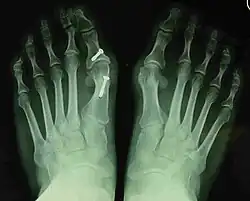

- For severe bunion deformity correction (Fig. 7)

- For recurrence correction after osteotomy procedure (Fig. 8)

Late deformity recurrence can happen after osteotomy (bone-breaking) procedures because osteotomy surgeries do not specifically stabilize first metatarsal bone.

For recurrence correction after fusion procedure (Fig. 9) Metatarsus primus varus deformity and pain recurred 6 months after modified Lapidus procedure and it could also be again corrected by the syndesmosis procedure.